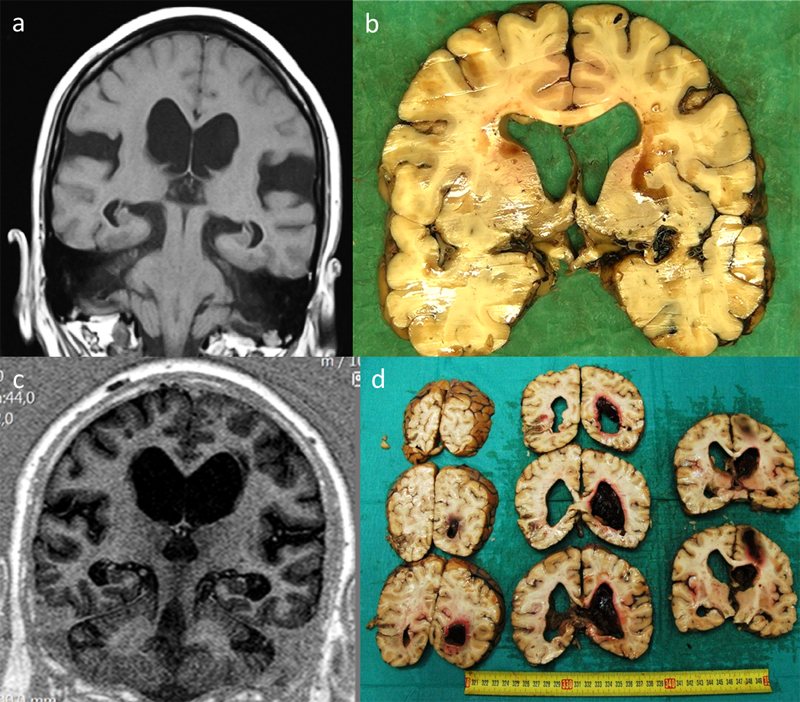

Figure 3. Radiological and post-mortem sectional findings. a: coronal MRI demonstrating ventricular enlargement pre-shunting, b: same case post-mortem section after shunting (time interval 2 years), c: coronal MRI demonstrating ventricular enlargement pre-shunting, d: intracerebral hematoma after the shunting procedure (time interval 3 months).

We present examples of radiological and post-mortem sectional findings in Figure 3. Table 6 is the case-by-case representation of the patients. Two subjects with disproportionate neuropathological findings to the degree of cognitive impairment at death are highlighted, representing cases of probable “hydrocephalic dementia”.